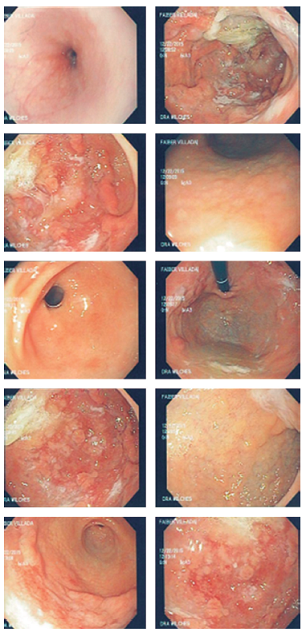

Fue evaluado por un gastropediatra, quien sospechó gastropatía perdedora de proteínas frente a enfermedad inflamatoria intestinal (por los hallazgos en TAC de abdomen), por lo que se programó para EDS y colonoscopia. Se encontraron pliegues corporales muy engrosados, mucosa corpoantral friable con pseudopólipos y erosiones, mucosa antral de aspecto folicular, bulbo duodenal y segunda porción con mucosa de aspecto normal, y la mucosa colónica tenía aspecto normal en toda su extensión (Figura 3).

Con estos hallazgos se sospechó EM y se solicitaron anticuerpos para CMV, los cuales reportaron con IgG e IgM reactivos, pero con carga viral para CMV negativa (77 ácido desoxirribonucleico [ADN]/mL).

El paciente evolucionó favorablemente luego del tratamiento diurético, la reposición con albúmina endovenosa, antisecretor y manejo nutricional; después de 9 días de hospitalización, se dio el alta para el manejo ambulatorio con esomeprazol y recomendaciones nutricionales. Asistió a consulta un mes después completamente asintomático y se revisaron los resultados de biopsia que reportó una gastropatía hipertrófica compatible con EM, 60 eosinófilos por campo y H. pylori negativo (Figura 4). Biopsias de mucosa colónica: inflamación crónica inespecífica.